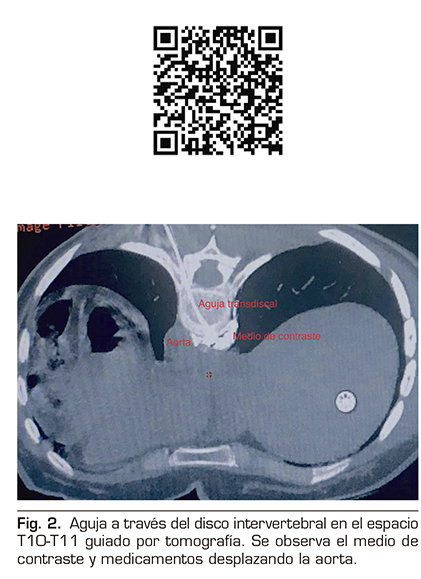

2.	Plancarte-Sánchez R, Máyer-Rivera F, Guillén Núñez MR, Guajardo-Rosas J, Acosta-Quiroz CO. Abordaje transdiscal de los nervios esplácnicos Cir Ciruj. 2003;71(3):192-203.